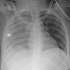

Chest x-ray of young girl suffering from #1 cause of death in children / adolescents in the U.S. Submitted by ohnoh18 t3_124kqok on March 28, 2023 at 10:49 AM in pics No comments 4